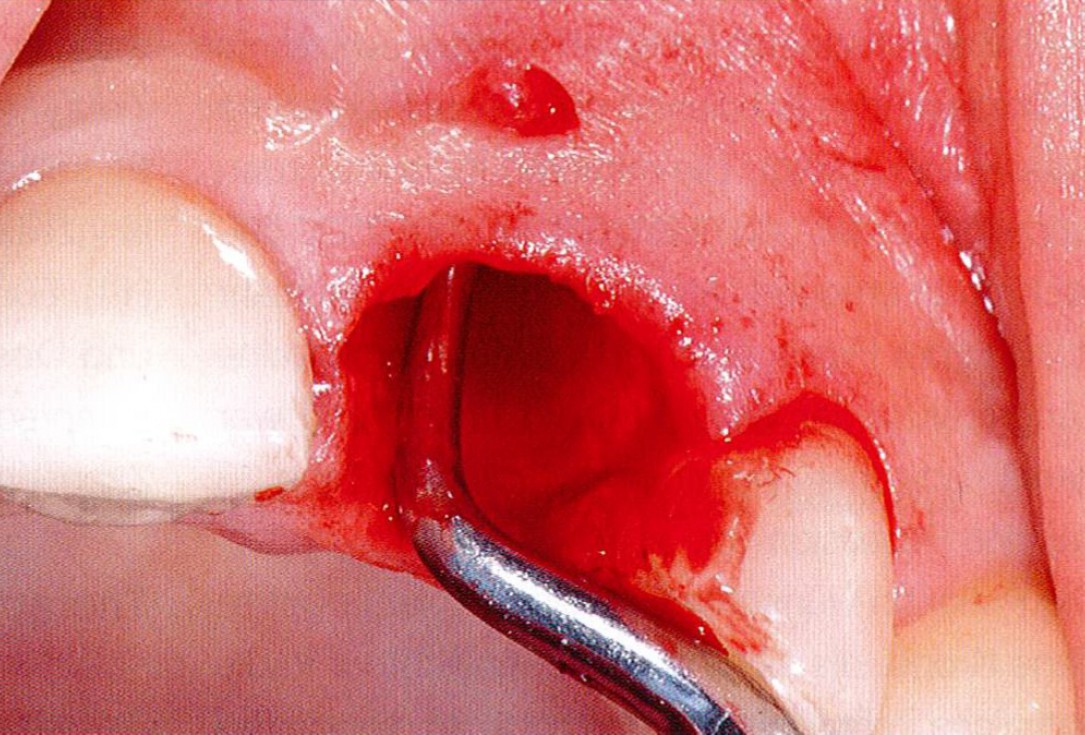

2/18 - Obvious loss of the buccal lamellaGBR together with soft tissue augmentation with mucoderm® and maxresorb® - Dr. S. Scherg